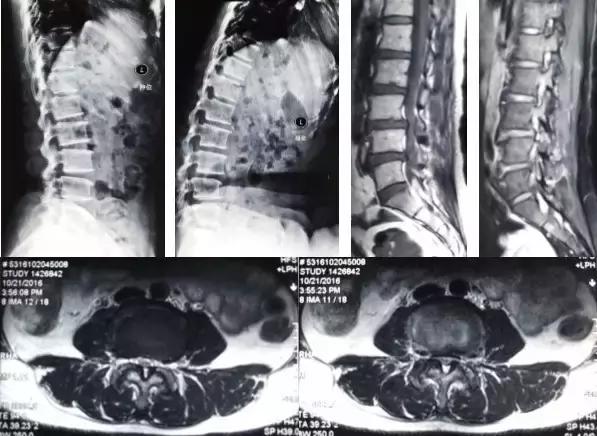

微创治疗退行性腰椎滑脱症

▲手术前